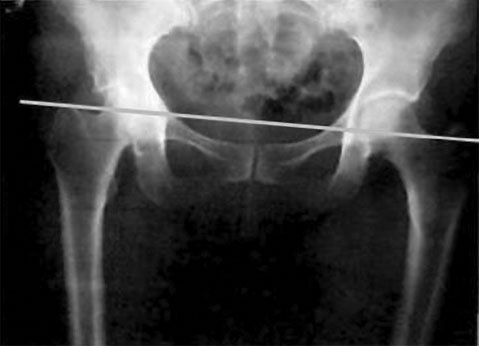

А теперь сравните его с рис. 16 – горизонталь, идущая по ним, перекашивается к левой ноге.

Рис. 16. Асимметрия таза

Видно, что уровень левой стороны (реальной стороны человека) ниже, чем правой. Значит, левая нога больше опирается на землю. Именно здесь нас поджидает дисбаланс под названием «опорная нога». На опорную ногу при ходьбе приходится бо́льшая часть веса человека.